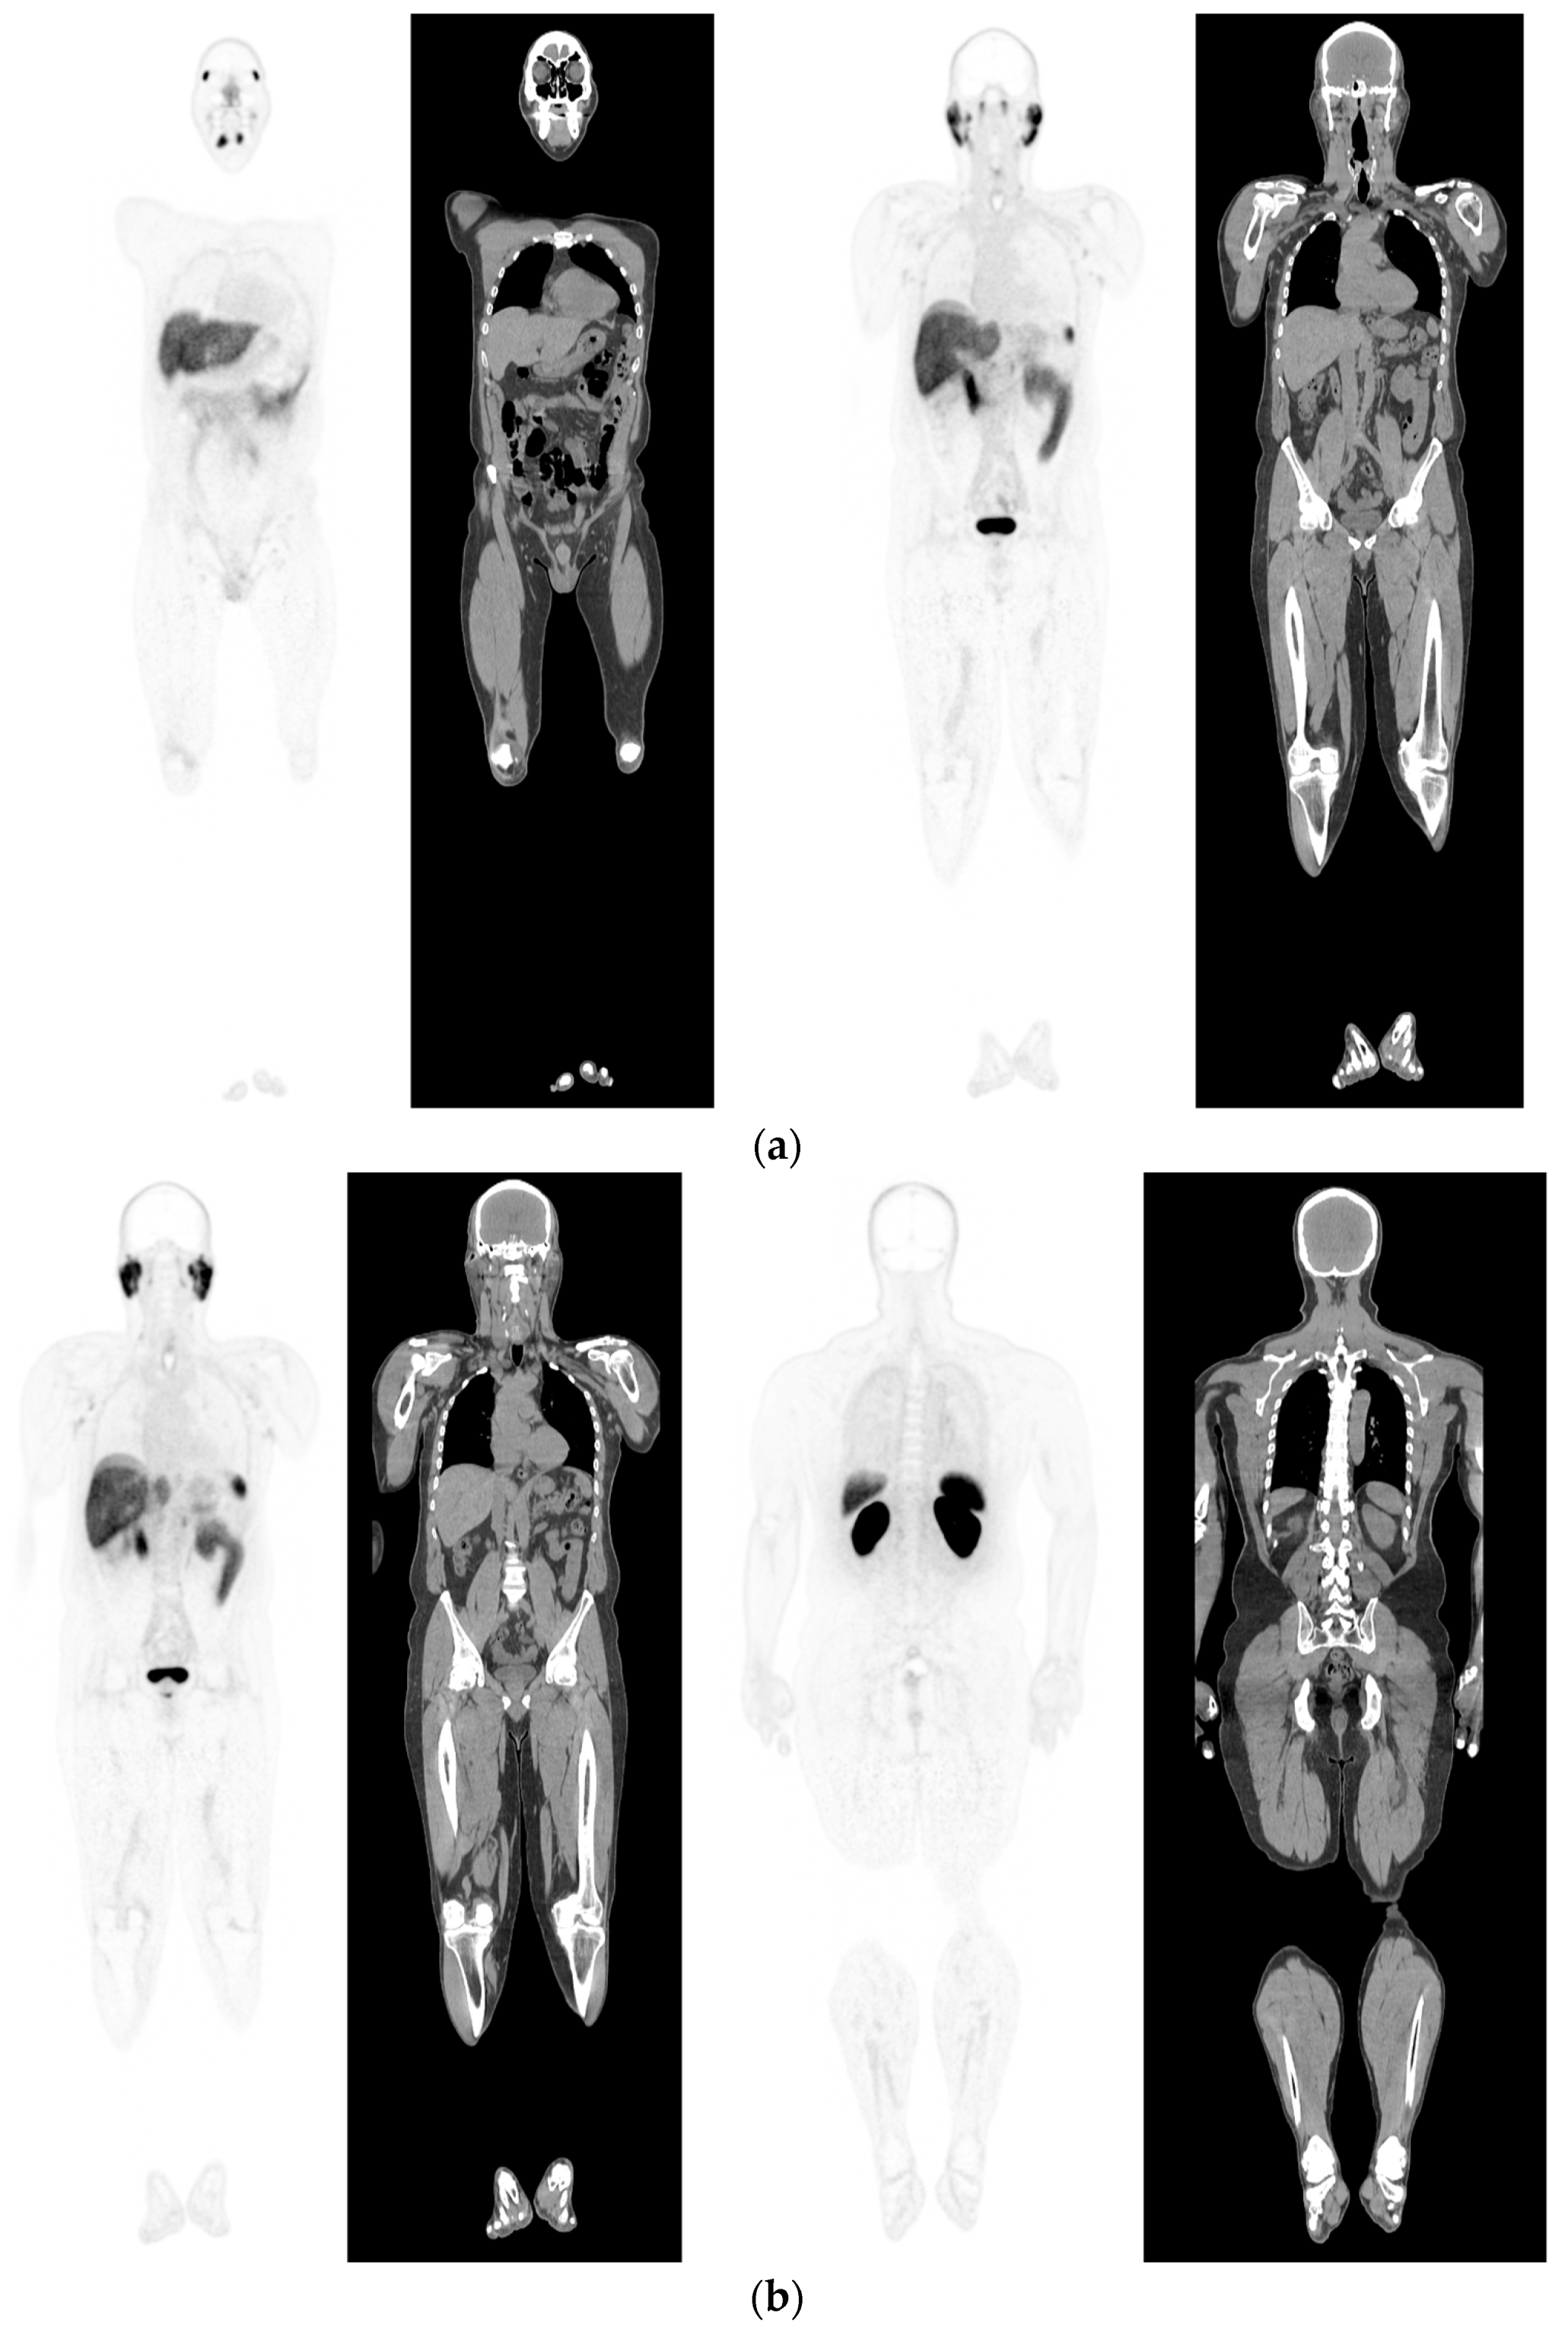

Figure 1.

PSMA PET-CT scan showing normal distribution of PSMA-11. 60 yr old M—Gleason 6 prostate cancer on active surveillance for past 2 years; PSA 7.2; MR imaging—low grade changes PIRADS 2. PSMA PET-CT: 68Ga-PSMA - 204 MBq; uptake 52 min; BMI = 29.7; Wt 90 Kg; coronal PET and corresponding CT slices (soft tissue windows) from left to right. (a)—physiological uptake in lacrimal, submandibular salivary glands, parotid glands, retropharyngeal soft tissue, liver, bowel, part of spleen and pooling of tracer in bladder; mild reactive tracer uptake in groin and axillary nodes. (b)—physiological uptake in head and neck; reactive uptake axillary nodes; focal uptake in apex of prostate gland anterior below the bladder SUV = 9.1; marked uptake/excretion of tracer in both kidneys.